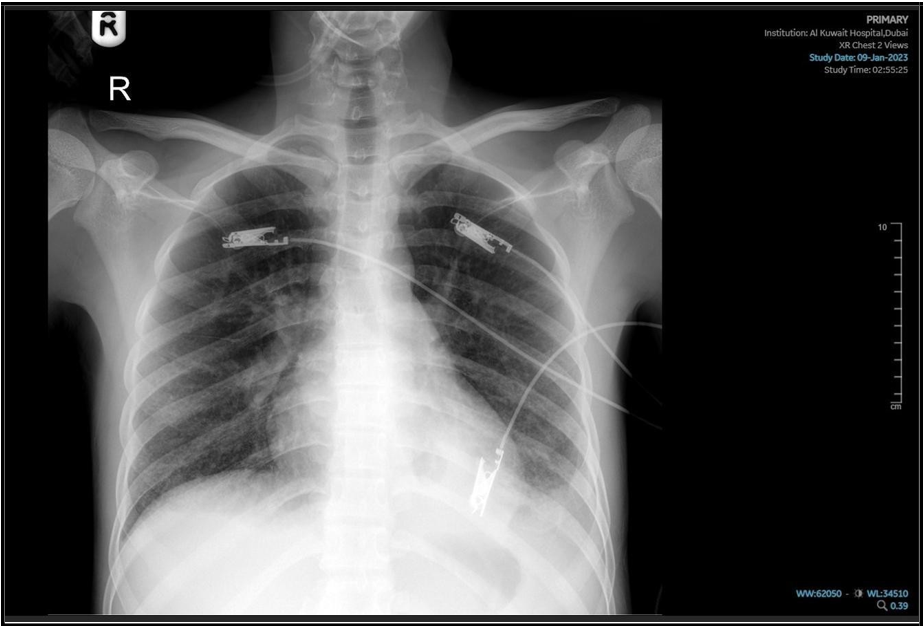

Due to the progression of symptoms— including worsening shortness of breath, a drop in SpO₂, and a generalized skin rash— the patient was transferred to the ICU and initiated on oxygen support. A repeat chest X-ray revealed features consistent with Acute Respiratory Distress Syndrome (ARDS). This was accompanied by a progressive rise in inflammatory markers (CRP increased to 154 mg/L, procalcitonin to 15 ng/mL), and a five-fold elevation in liver transaminase levels. Viral screening tests for Measles, Epstein-Barr Virus (EBV), Cytomegalovirus (CMV), and Rubella were requested and all returned negative. The Electrocardiogram (ECG) was unremarkable, and echocardiography revealed normal wall motion and thickness, with a preserved ejection fraction of 55%. However, Pro-BNP was markedly elevated at 3000 pg/mL. Following evaluation by the infectious disease consultant, first-line anti- tuberculous medications were discontinued, and second-line anti-TB therapy was initiated along with a course of corticosteroids.

(“03 Jan. 2025”), Progressive patchy alveolar infiltrate, moderate Rt side effusion.

He kept on—based on the availability of second-line agents—with Imipenem-cilastatin, levofloxacin, linezolid, and prednisolone, along with the continuation of ethambutol and ongoing oxygen support. After a few days, his condition stabilized, and he was gradually weaned off oxygen support before being transferred back to the medical ward. His inflammatory markers showed progressive improvement, and liver enzyme levels returned to normal.

(“16 Jan 2025”) Significant changes noted, with improvement of patchy alveolar infiltrate, still hazy left CP angle.